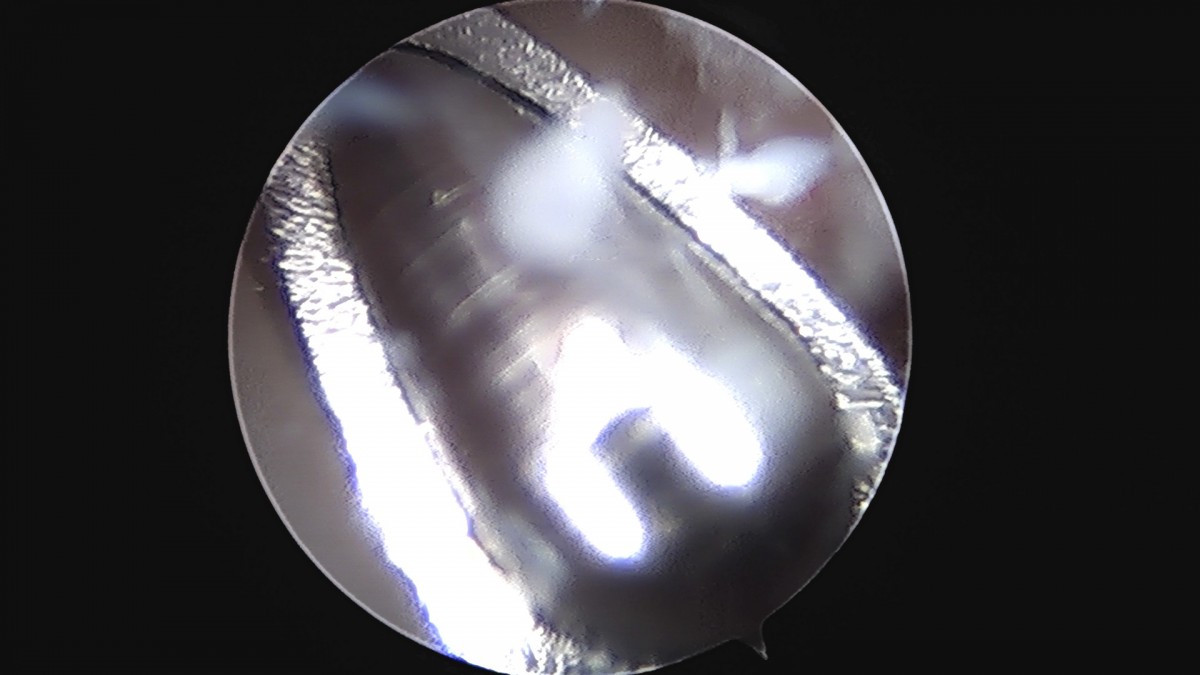

정지영원장님 손목 삼각섬유연골 복합체 봉합술 박현O 환자

dae765e4d9ac96aee867c9d6292d8784_1758009003_6955.jpg

dae765e4d9ac96aee867c9d6292d8784_1758009004_2826.jpg

dae765e4d9ac96aee867c9d6292d8784_1758009004_9063.jpg

dae765e4d9ac96aee867c9d6292d8784_1758009005_5023.jpg

dae765e4d9ac96aee867c9d6292d8784_1758009006_0987.jpg

dae765e4d9ac96aee867c9d6292d8784_1758009006_6871.jpg

dae765e4d9ac96aee867c9d6292d8784_1758009007_2899.jpg

dae765e4d9ac96aee867c9d6292d8784_1758009007_8815.jpg

dae765e4d9ac96aee867c9d6292d8784_1758009008_4621.jpg

dae765e4d9ac96aee867c9d6292d8784_1758009009_0494.jpg